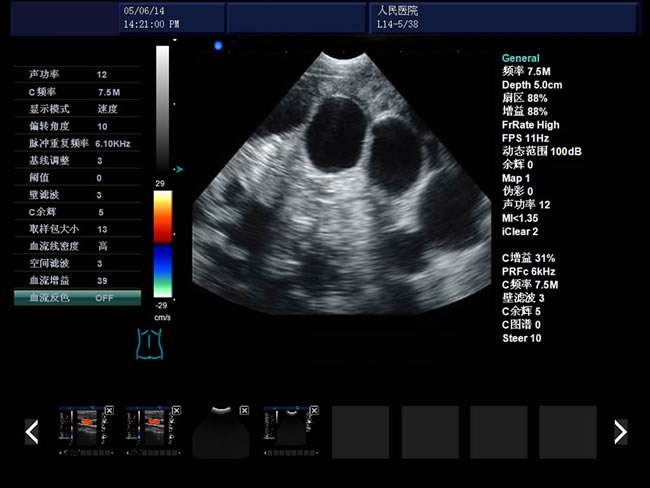

S9 彩色多普勒獸用超聲診斷儀

• S9彩色多普勒獸用超聲診斷儀是徐州市大為電子設備有限公司推出的一款全新的彩色超聲診斷儀器。

血流圖像:頻譜:B/D、B/C/D CFM:B|C|D、B|C|M、B|C雙實時、PW、CFM、CPA

彩色血流圖像調節參數:多普勒頻率、取樣框位置和大小、基線、彩色增益、偏轉角度、壁濾波、累積次數等。